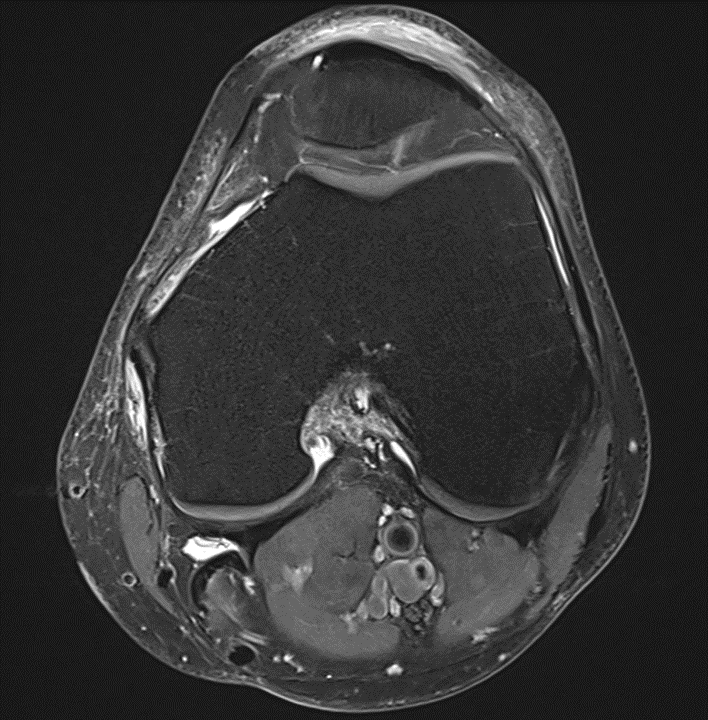

Sie sehen folgendes MRT-Bild eines Patienten unter Therapie mit Ipilimumab. Um welches Krankheitsbild handelt es sich und welche andere Untersuchung könnte man durchführen um andere Nebenwirkungen des Medikamentes auszuschließen?